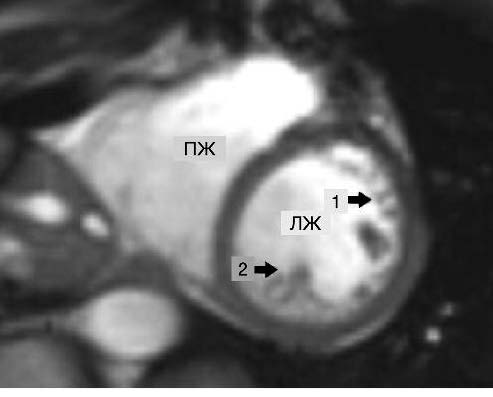

Совокупность клинической информации, данных лабораторно-инструментальных методов исследования при поступлении, быстрая положительная ЭхоКГ-динамика позволили подтвердить диагноз СТ. Для подтверждения диагноза НМЛЖ через 2 мес выполнена МРТ сердца (рис. 6, 7).

Рис. 6. МРТ сердца, короткая ось, срез на уровне средней трети ЛЖ: 1 – некомпактный слой миокарда; 2 – трабекула.

Примечание. ПЖ – правый желудочек.

Рис. 7. МРТ сердца, четырехкамерный вид. Стрелкой указаны трабекулы.

Примечание. ЛП – левое предсердие, ПП – правое предсердие.

Заключение: МР-картина повышенной трабекулярности миокарда ЛЖ, конечно-диастолическое соотношение некомпактного и компактного слоев миокарда менее 2,3. При исследовании в кинорежиме нет изменения сократительной способности ЛЖ, что также исключает НМЛЖ, в остальном – без патологических изменений; отсутствие участков патологического накопления контрастного препарата при отсроченном сканировании исключает перенесенный инфаркт миокарда, что подтверждает СТ.

В 2005 г. S. Petersen и соавт. предложили следующий критерий НМЛЖ по данным МРТ: соотношение толщины некомпактного и компактного слоев миокарда ЛЖ более 2,3; измерение проводится по длинной оси на уровне между митральным клапаном и верхушкой ЛЖ в конце диастолы [2]. В том случае, когда толщина некомпактного слоя не соответствует принятому в настоящее время критерию, изменения в миокарде нужно расценивать как повышенную трабекулярность ЛЖ. Однако, по мнению ряда авторов, в основе повышенной трабекулярности ЛЖ могут лежать те же генетические причины, что и при развитии НМЛЖ, поэтому трансформация гипертрабекулярности в НМЛЖ может быть лишь вопросом времени [3].

В нашем случае у пациентки по данным МРТ сердца диагноз НМЛЖ исключен и выявлена повышенная трабекулярность миокарда ЛЖ. Возникает вопрос: сосуществовали ли эти два состояния – гипертрабекулярность ЛЖ и СТ или они имели патогенетическую взаимосвязь?